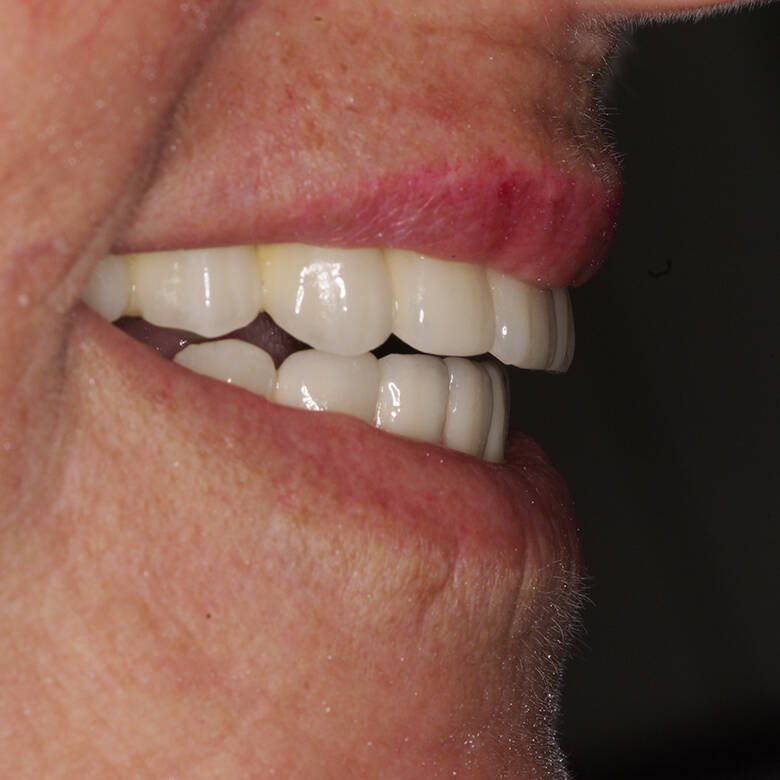

- Recuperação rápida: O paciente sai do consultório com um sorriso renovado em questão de dias.

- Conforto e Estética: A prótese provisória é funcional e visualmente semelhante aos dentes naturais.

- Melhora da autoestima: O impacto positivo de um sorriso completo é imediato, melhorando a qualidade de vida.